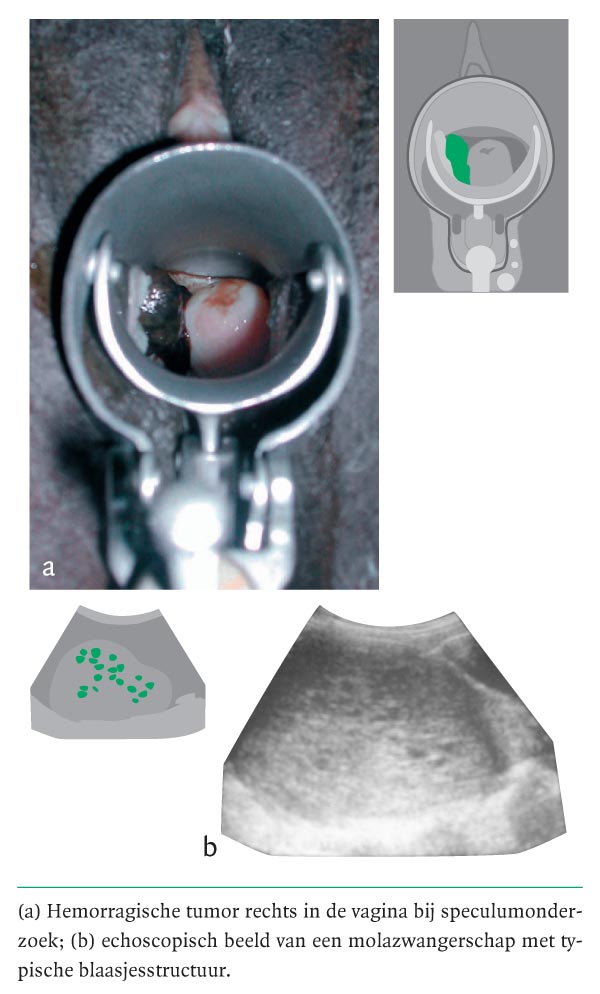

Een 19-jarige primigravida presenteerde zich op de eerstehulpafdeling met vaginaal bloedverlies bij een amenorroeduur van ongeveer 4 maanden en een positieve zwangerschapstestuitslag. Bij lichamelijk onderzoek werd een niet-bleke vrouw gezien die een gezonde indruk maakte; de fundushoogte was conform 14 weken zwangerschap. Speculumonderzoek toonde een hemorragische tumor met een diameter van 2 × 3 × 3 cm rechts in de vagina (figuur a). Differentiaaldiagnostisch werd gedacht aan een traumatische laesie met mogelijk geïnduceerde abortus, een hemorragische poliep of een vaginaal neoplasma. Bij abdominale echografie werd een typische blaasjesstructuur gezien, passend bij een mola hydatidosa (zie figuur b